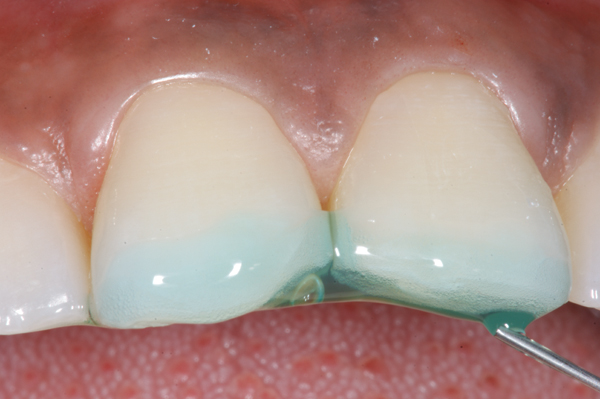

Fig 7. Maxillary incisors etched with phosphoric acid etchant.

Figure 7